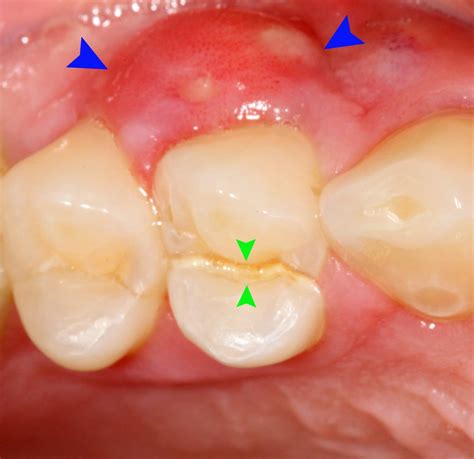

Gum boils are localized infections that form in the gum tissue. They often appear as small, pus-filled bumps that can be quite painful. These infections can develop rapidly and, if left untreated, can lead to more serious oral health issues. The primary causes of gum boils include:

• Pus-filled bumps on the gums

• Redness and tenderness in the affected area